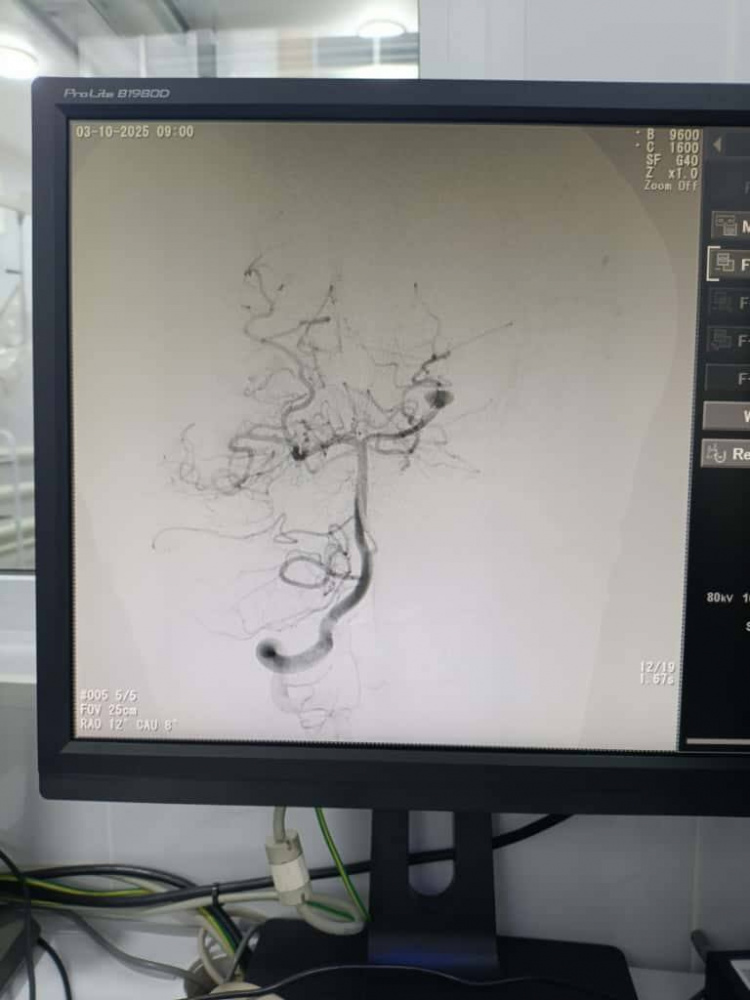

Каждое вмешательство проводилось под общим наркозом с постоянным контролем жизненно важных функций. На дооперационном этапе выполнялась ангиографическая диагностика, позволившая определить размеры и расположение сосудистых аномалий и выбрать оптимальную эндоваскулярную тактику для каждого пациента.

При лечении аневризм выполнялась эндоваскулярная окклюзия с сохранением проходимости магистральных сосудов, а при артериовенозных мальформациях - точечная эмболизация патологического узла для предотвращения риска кровоизлияния. Все манипуляции осуществлялись под контролем цифровой субтракционной ангиографии.

После операций была проведена контрольная ангиографическая оценка, подтвердившая успешное выключение патологических очагов из кровотока и отсутствие осложнений. Все дети благополучно вышли из наркоза и переведены в отделение реанимации для наблюдения. По данным врачей, состояние пациентов стабильное, осложнений не отмечено, восстановление проходит активно.